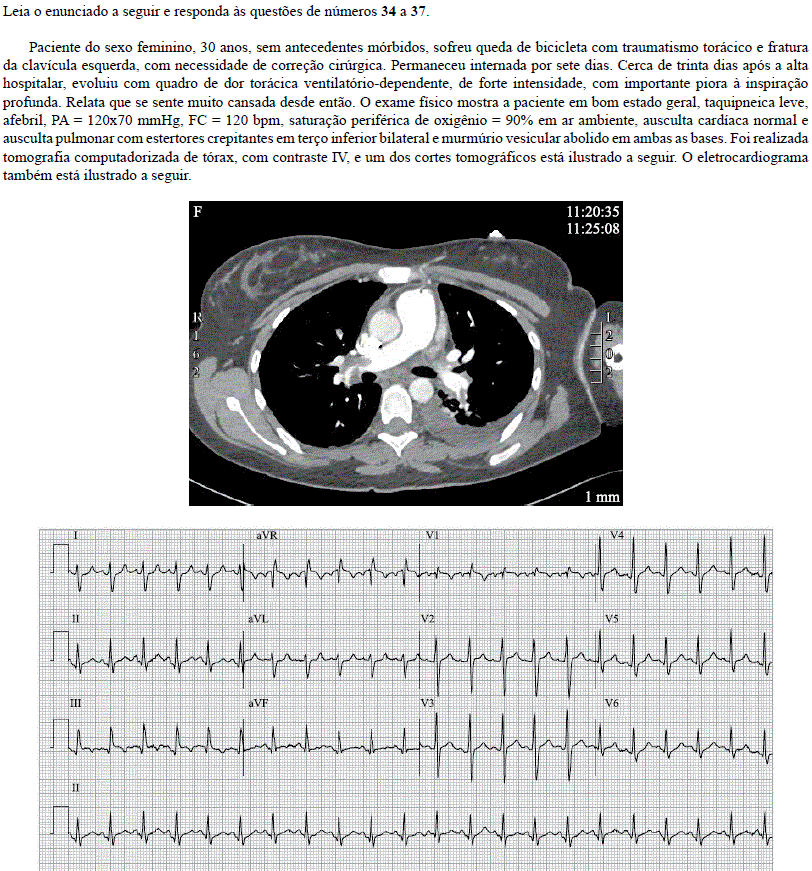

O mecanismo fisiopatológico que melhor explica a intercorrência ocorrida é

Assinale a alternativa que contém a melhor opção terapêutica para a paciente em questão.

O diagnóstico mais provável é de